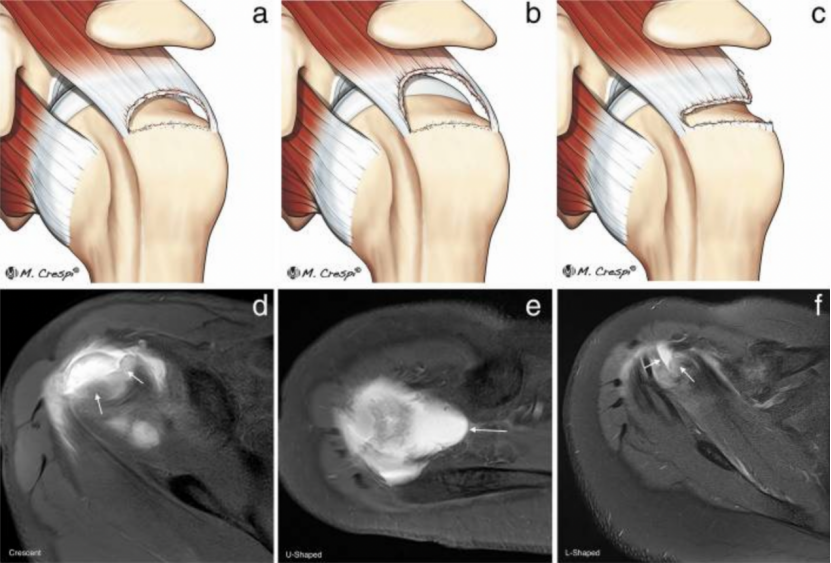

2、双排操作要点

内排锚钉先置入并收线减张,确认肌腱可无张力覆盖足印区后,再置入外排锚钉。外排推荐无结锚钉(knotless),以减少线结在肩峰下的撞击风险。

为什么会有单关节器械关节镜下肩袖修复:单排 vs 双排缝合,如何选择?_https://www.jmylbn.com_新闻资讯_第13张

图 12:双排改良 Mason-Allen 缝合技术(单结)。图源:文献 6

外排锚钉置入点位于大结节外侧缘,与内排形成有效桥式覆盖;内外排缝线走向应尽量平行于肌腱纤维,避免斜行切割。需特别警惕外排 「 过度加压 」,界面压力过大可能损害肌腱远端血供,反而影响愈合质量。